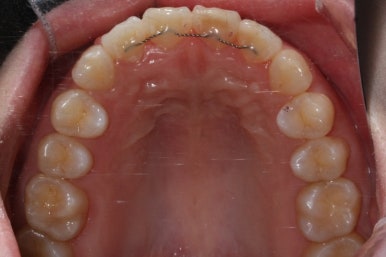

부산앞니교정 키다리아저씨치과에 처음 내원하셔쓸 당시의 입안 모습입니다.

앞니가 살짝 삐뚤어진 것을 볼 수 있고, 삐뚤어진 사이에서 약간의 틈새도 있었습니다.

예전에 치료 받으셨던 앞니 부분에 약간의 변색도 와서 미적으로 좋지 못한 상황이였습니다.